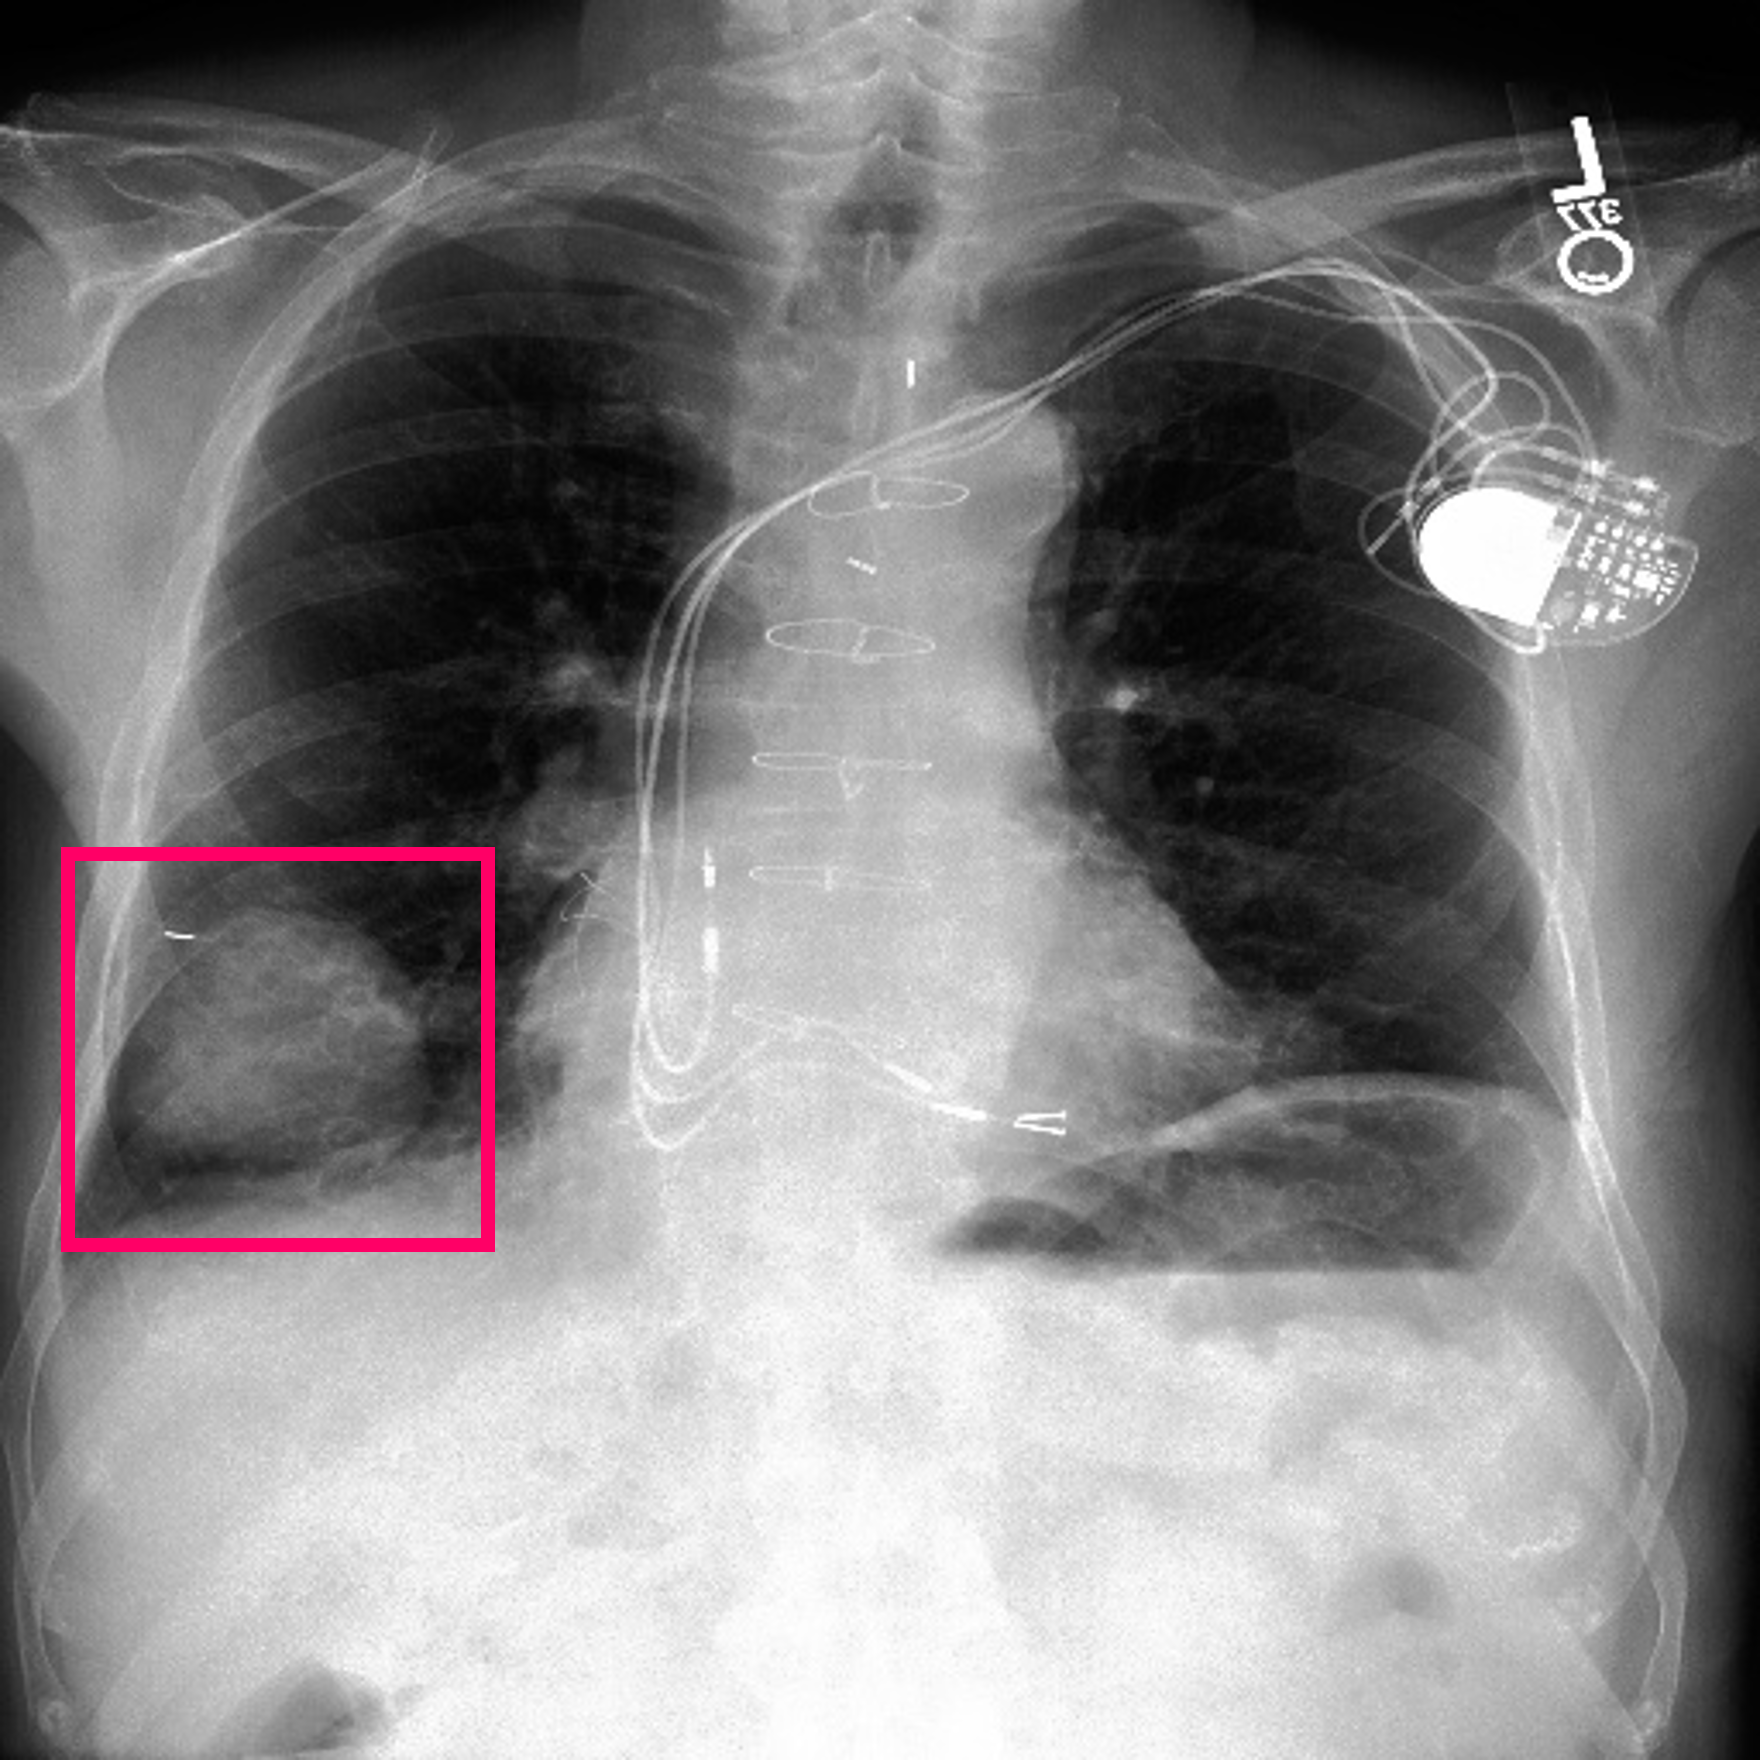

3.3 Interpretability

Post-Hoc Comparisons. We compare our concept-based explanations to post-hoc XAI techniques LIME and SHAP, applied to the baseline InceptionV3 model. The image explanations generated by these techniques disagree with each other and the medical ground truth. We show an example of this observation in Figure 7, where both techniques fail to capture the large mass in the X-ray, and highlight irrelevant regions such as areas outside of the lung as incorrectly important to the classification decision. In contrast, our approach correctly identifies the presence of a mass. More examples are shown in Figure 10.

Refer to caption

(a) Ground Truth

(b) LIME

(c) SHAP

(d) CXR-LLaVA Generated Report

(e) Our Approach

Figure 7: Example of our explanation approach outperforming LIME, SHAP and CXR-LLaVA. Ground truth (a) is a “Large right upper zone mass". LIME (b) and SHAP (c) fail to capture the mass in the X-ray. Most important image regions are bounded by yellow for LIME, and shown in more vibrant green for SHAP. CXR-LLaVA (d) generates a report which wrongly describes the image as non-cancerous. Our approach (e) correctly identifies the presence of a mass.